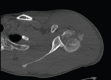

Introduction: Posteriorly dislocated humeral head fracture has a great implication, as it is associated with high risk of avascular necrosis, limited access through the deltopectoral approach, and posterior approach to the posteriorly dislocated humeral fracture increases the risk to the remaining blood supply.

Technical tip: Posteriorly dislocated humeral fracture is approached through deltopectoral approach. Schanz pin is inserted into the humeral head to achieve purchase in the humeral head. Applying laterally directed force the humeral head is disengaged from the lateral margin of glenoid. A rotatory force then repositions the humeral head into a congruous position. Open reduction internal fixation is then carried out in a standard fashion.

Conclusion: Retrieving the humeral head from the posteriorly dislocated position in patients with posterior fracture dislocation of the shoulder can be challenge to a trauma surgeon. With this novel technique, humeral head is reduced through deltopectoral approach without increasing the risk to the remaining blood supply.